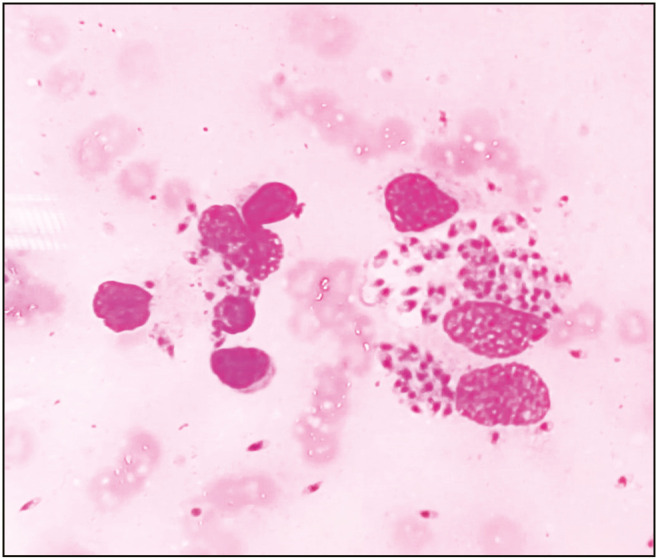

Leishmaniasis is an endemic health issue in tropical and subtropical countries and is a protozoal disease caused by leishmania species. The most common clinical type of leishmaniasis is cutaneous leishmaniasis (CL), and its diagnosis requires confirmation by laboratory tests since treatment for the condition necessitates long-term medication and poses a risk of harmful drug exposure. In developing nations, advanced diagnostic tools like molecular procedures and culture are not available in all centers. The conventional scraping procedure stained by Giemsa is the most preferred diagnostic tool used extensively. This case report highlights the importance of scrape cytology in the diagnosis of CL.